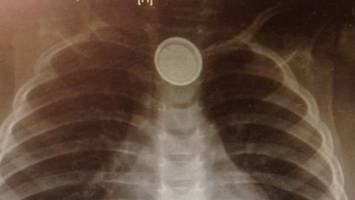

خبر: به گفته پزشکان در صورتیکه این باتریهای دکمهای به طور تصادفی توسط کودک بلعیده شود در مری گیر کرده و در بافت آن سوختگی ایجاد میکند.

پزشکان به والدین توصیه میکنند باتریهای دکمهای همچون مواد سمی برای کودک خطرزا هستند و باید دور از دسترس آنان قرار گیرد.

یک متخصص جراحی اطفال در انگلیس گفت: در صورتیکه این باتریها با مخاط مری پوشانده شود میتواند یک مدار الکتریکی بوجود آورده و باتری فعال شود که این یکی از مشکلات ناشی از بلعیدن باتریهای دکمهای است.